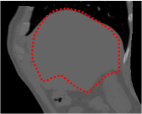

An example of CT/CBCT and MR/CBCT registration results are shown in figures 3 and 4, respectively. For both cases, the CBCT image (first column) was acquired intra-operatively after needle insertions and was employed as a reference for image registration. The pre-operative image is displayed before registration (second column), after PM-EA (third column) and after PM-EA+Evo (fourth column). The occurrence of patch shifts is reported for each spatial direction in panels (m–o): for each histogram, the shift with maximal occurrence is shown by the red dashed line. For panels (a–l), a ROI — manually defined on the CBCT image/encompassing the liver — is shown using red dash lines. Our visualization shows an improved correspondence of the contour of the liver with the manually defined liver boundary when the PM-EA solution is employed (see 3(c,g,k) and 4(c,g,k)). Moreover, an even better correspondence of the contour is observable using the PM-EA+Evo solution (see 3(d,h,l) and 4(d,h,l)).

Trans.

[X-Y]

CBCT

(a)

CT / No registration

(b)

CT / PM-EA

(c)

CT / PM-EA+Evo

(d)

Sag.

[X-Z]

(e)

(f)

(g)

(h)

Cor.

[Y-Z]

(i)

(j)

(k)

(l)

(m)

(n)

(o)